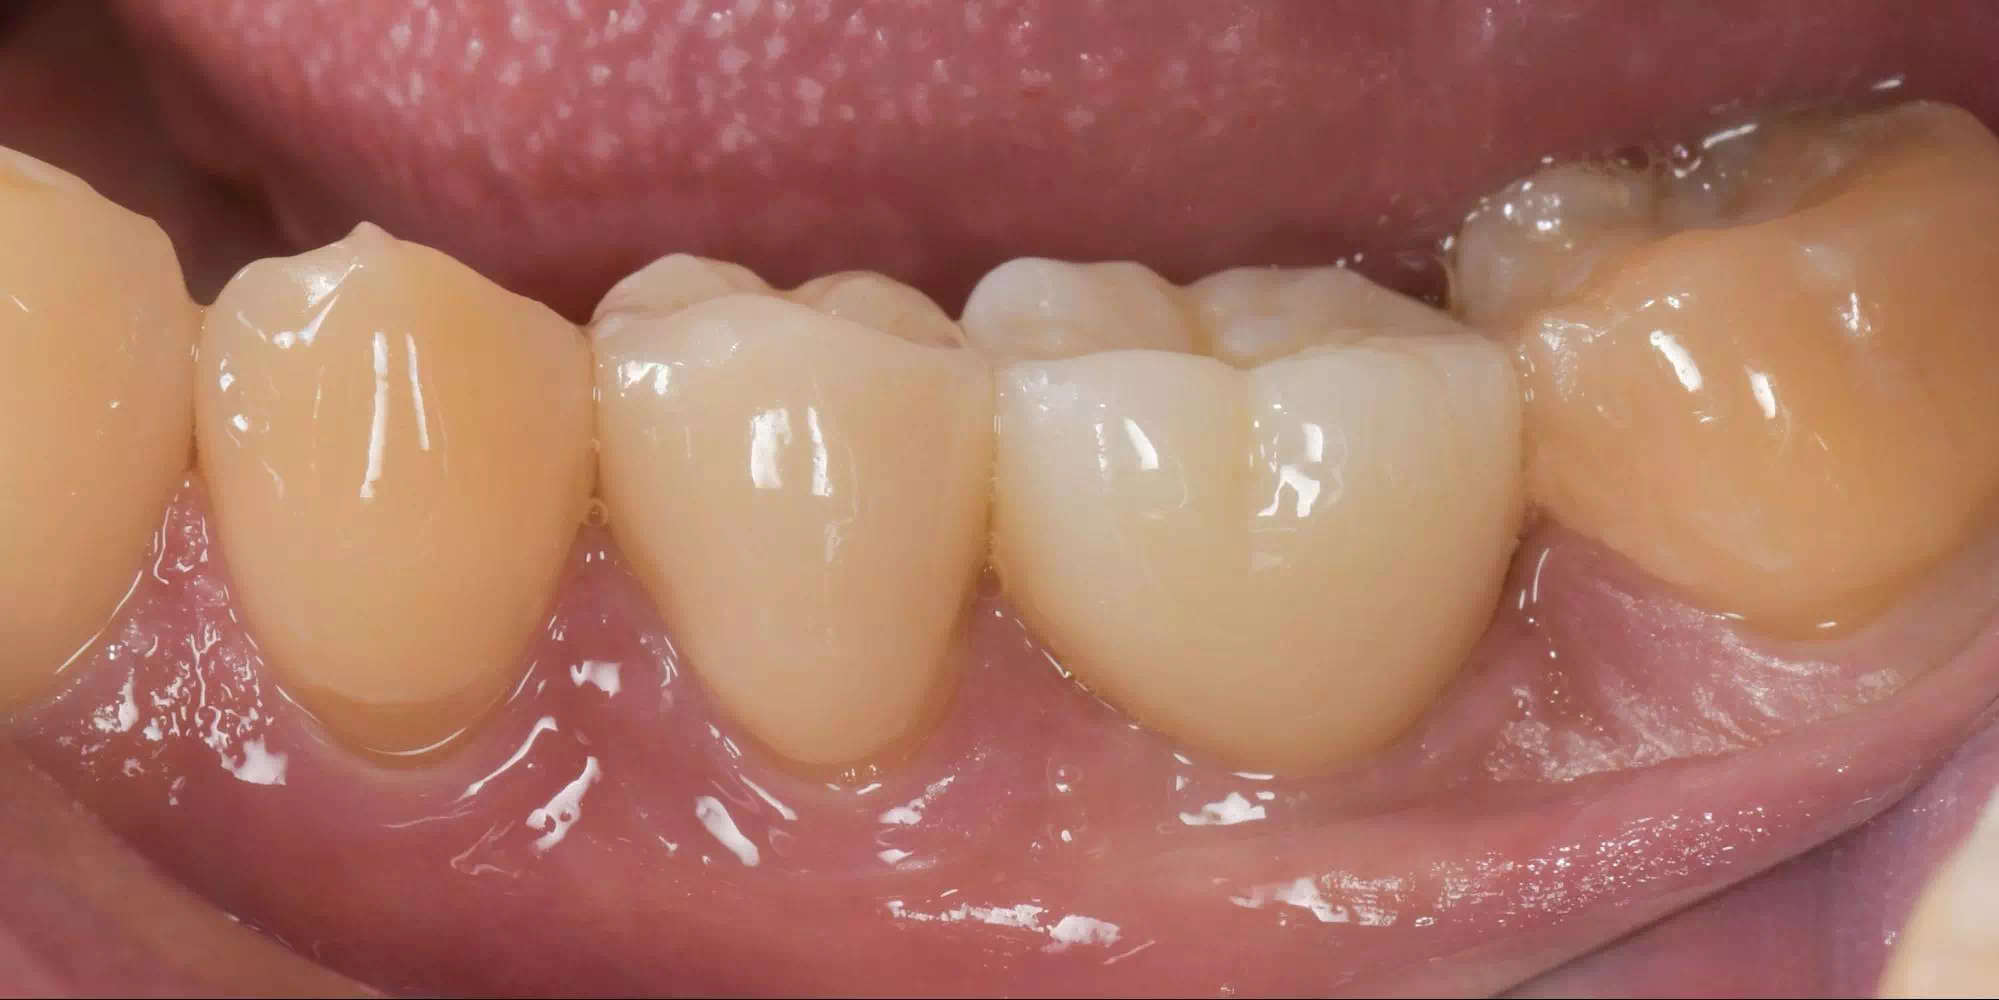

CASE HOME CASE 2025/10/21 抜歯即時埋入・即時荷重 症例 2025/10/21 GBR① 2025/10/21 インプラント 症例② 2025/10/21 インプラント 症例① 2025/10/21 矯正歯科 症例 2025/10/21 審美歯科 症例② 2025/10/21 審美歯科 症例① 2025/10/21 ガミースマイル 症例 2025/10/21 歯肉再生 症例② 2025/10/21 歯肉再生 症例① 2025/10/21 虫歯症例